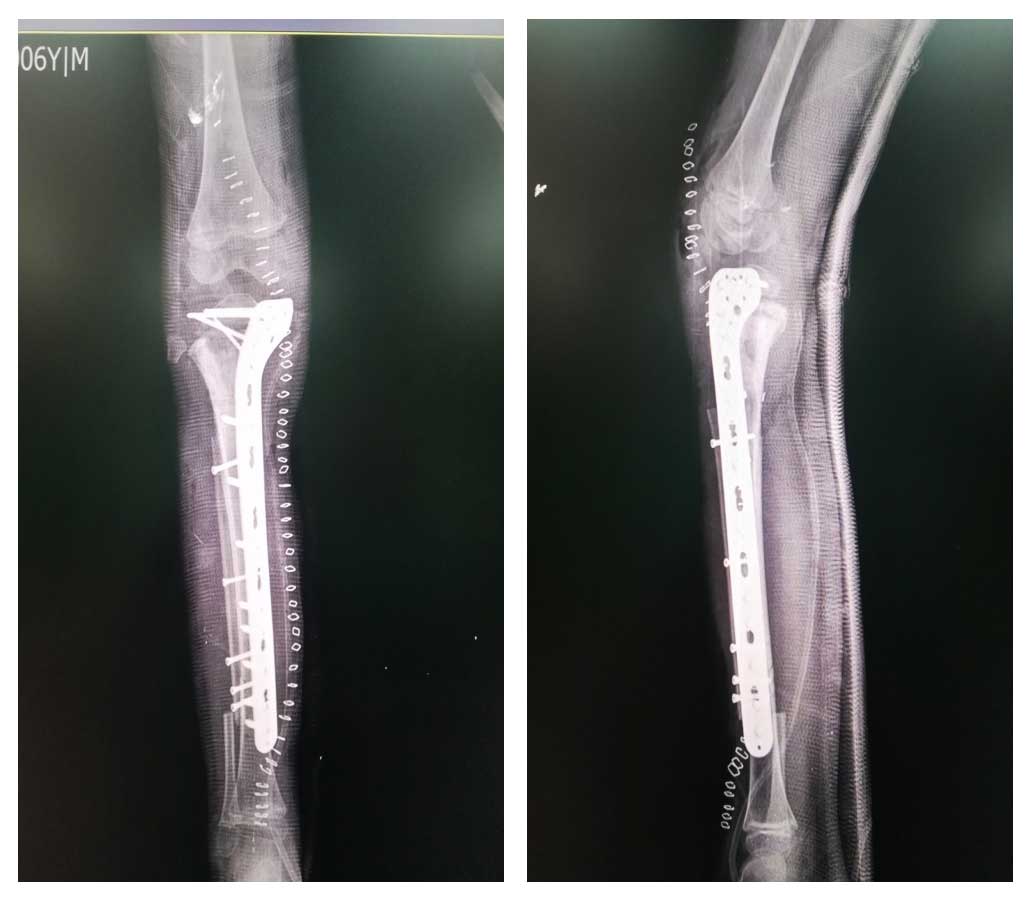

Ameliyat Sonrası: Röntgende rezeksiyon sonrası geri kazanılmış kemik ve fibulanın titanyum anatomik plak ile fiksasyonu görülmekte.